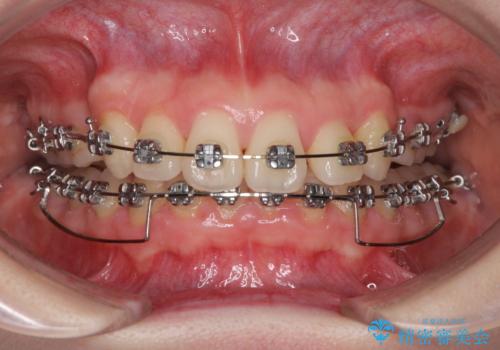

- 矯正装置

- メタルブラケット

上顎の左右第一小臼歯2本を抜歯し、ワイヤー装置にて歯列を整えることとしました。

奥歯の咬み合わせがなかなか定まらず、スペースが閉じるまでに時間がかかりましたが、最終的には正中を合わせることもできました。